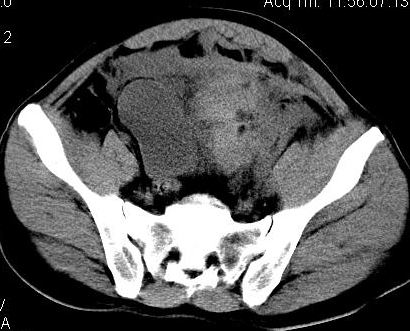

标题: CT8132:转贴:男,38岁,腹部压伤后腹痛、休克入院检查。 [打印本页]

标题: CT8132:转贴:男,38岁,腹部压伤后腹痛、休克入院检查。

盆腔血肿可能性大

盆腔内巨大血肿

考虑盆腔内血肿

本例支持盆腔左侧巨大血肿。

盆腔左侧不均匀高密度影,周围锐利,与膀胱分界清晰,考虑肠系膜损伤盆腔内血肿形成。期待结果。

盆腔内巨大血肿,患者是否有骨盆骨折?

结果公布:腹膜外血肿和腹腔内出血,虽然都是出血,但诊断和治疗却截然不同。如果腹腔内出血,那么在输血抗休克同时还要急诊手术止血。而腹膜外血肿不同,因为腹膜外出血往往都是小静脉丛破裂出血,手术往往找不到出血部位,找到了也很难缝合止血,造成难以控制的大出血,危机病人生命。还有腹膜对出血有个束缚作用,相当于压迫止血,利于出血自止。所以对腹膜外出血往往采取保守治疗。当然,如果腹膜外出血止不住破入腹腔,那么病人往往预后极差,恐怕连“九死一生”都谈不上。

ct上鉴别两者:腹腔内出血没有固定形态,分散在腹腔内,肠间隙等部位,破裂出血处会有较多血液聚集有血块;由于膀胱直肠陷凹是腹腔的最低处,出血和积液会积聚在此处,液体较多时膀胱会呈向前受压改变。该片血肿可见包膜(其实是腹膜)膀胱向右侧受压移位,而膀胱是腹膜间位器官。所以诊断是腹膜外血肿。